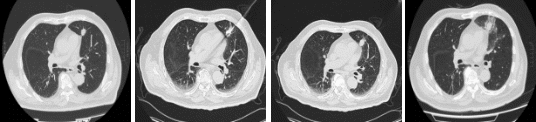

近日,上海市东方医院肿瘤科周彩存教授团队成功为一名高龄、肺功能基础差且病灶紧贴心脏的肺癌患者实施了机器人辅助下经皮穿刺消融手术